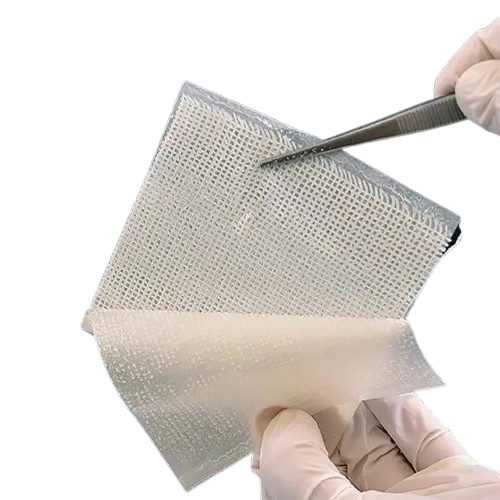

Chlorhexidine Gauze Dressing

Chlorhexidine Gauze DressingOur ProductsFrom SurgicaveUplode:9 months ago from India